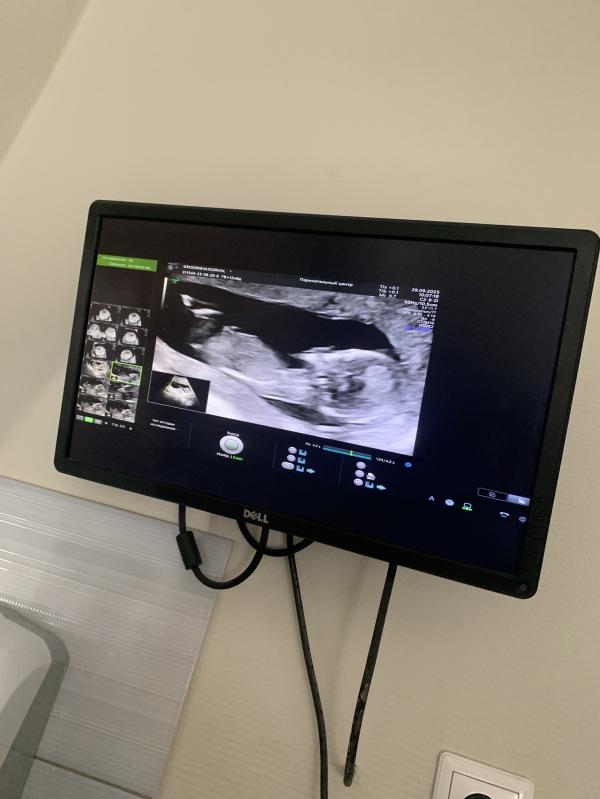

Моя внутренняя чуйка говорит мне что это мальчик😍🥹

Первый этап пройден, по скринингу все хорошо, ждем результаты крови

100% парень 👌 волшебную палочку уже отчётливо видно👌😁